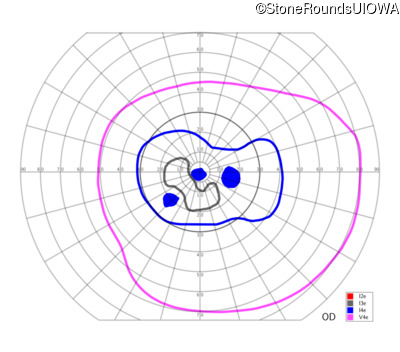

Congenital Stationary Synaptic Dysfunction (IA2g)

Congenital Stationary Synaptic Dysfunction (IA2g)

| Congenital Stationary Synaptic Dysfunction | CABP4 | Arg49Stop CGA>TGA | IVS1+1 G>T | AR |